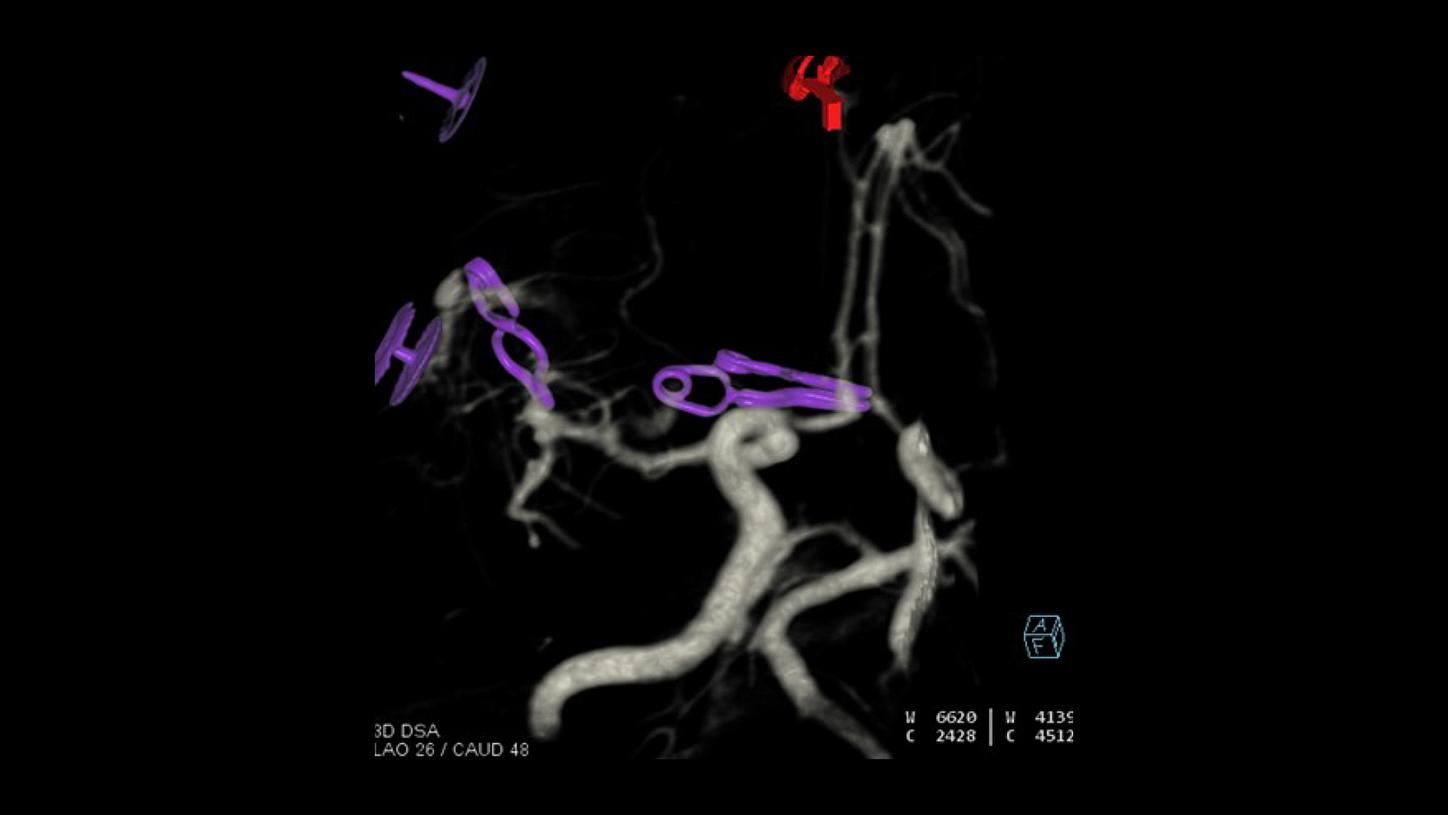

- Follow-up syngo DynaCT after clipping, with intravenous contrast media injection

- Follow-up syngo DynaCT after clipping, with intravenous contrast media injection

- Dual-volume vessel presentation of the clipped aneurysm

- Follow-up syngo DynaCT after clipping, with intravenous contrast media injection

- Follow-up syngo DynaCT after clipping, with intravenous contrast media injection

- Dual-volume vessel presentation of the clipped aneurysm